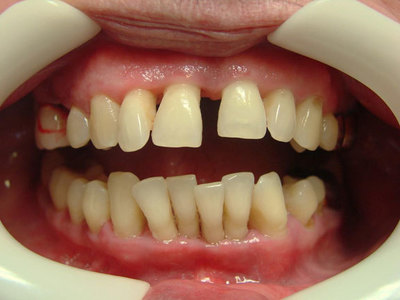

Для течения пародонтита характерны 3 стадии, и симптоматика меняется по мере прогресса заболевания:

- Признаки пародонтита в лёгкой степени совсем незначительны. Дёсны воспалены, в процессе чистки зубов умеренно кровоточат, но без болевых ощущений. Пока не поражена пародонтальная связка, процесс заболевания считается обратимым.

- На средней стадии пародонтита кровоточивость значительно увеличивается, возможны ощущения зуда и жжения. Десна отекает и меняется в контуре, а размер кармана десны доходит до 6 мм.

- Переход в тяжёлую форму пародонтита сопровождается стремительным разрушением костной ткани, зубы теряют опору, веерообразно расходятся и шатаются. На данной стадии заболевания появляется резкий гнилостный запах изо рта, нарушается жевательная функция, и выпадают первые зубы. Глубина кармана десен превышает 6—7 мм.